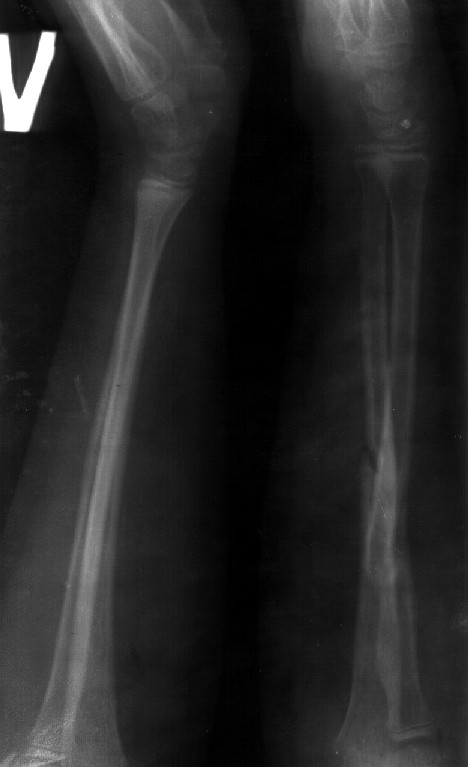

СМ> Сделал симметричные снимки с максимальной супинацией и пронацией при

СМ> согнутом предплечье в 90 град. Объем ротационных движений 90-100 град.

Снимок один сделан с супинацией, второй - оба предплечья в одинаково нейтральном положении. то есть по этим снимкам объем ротационных движений не оценить. Снимко в двух проекциях лучше и делать в среднем положении между пронацией и супинацией, то есть обе проекции в однм и том же положении, когда линия, проходящая через шиловидные отростки, идет в плоскости головки. Прошу прощения за усложнение простых вещей.